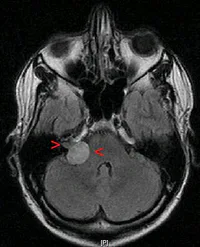

Caso 1: Paciente masculino de 63 años, quien no refiere antecedentes. Presenta únicamente un shwannoma vestibular (neurinoma del acústico) de 11 años de evolución. De acuerdo a lo anterior la lesión se encuentra en:

De acuerdo al caso 1, presenta esta audiometría, de la cual se puede afirmar: